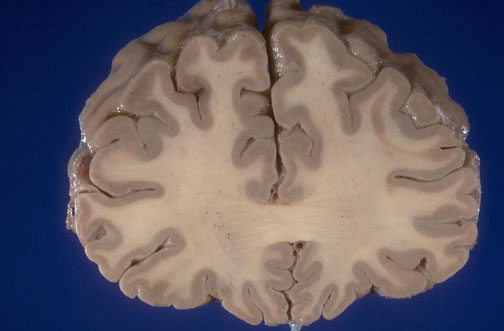

Identify the following regions of the normal brain, viewed here looking anterior to posterior, in the image above: Left superior frontal gyrus - Left middle frontal gyrus - Left inferior frontal gyrus - Gyrus rectus - Genu of corpus callosum